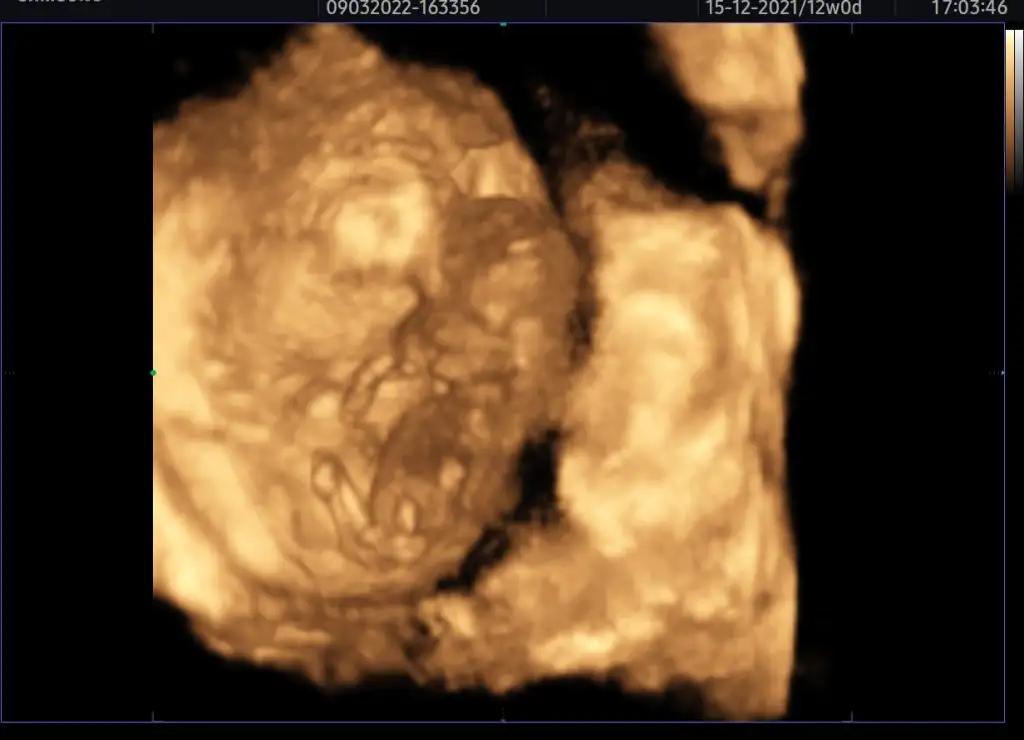

İnsan her baktıgında duygulanıyor.İnşallah dogum hikayemizi anlatacagımız günler gelicekKizlarrrr benim minnoşuma bakın yaa rabbimize ne kadar şükretsek az şu nimet için her baktığımda eriyorum 2.olmasına rağmen duygular hep aynı rabbim hayırlısıyla sağlıkla kucaklarımıza aldığımız günleri de göstersin